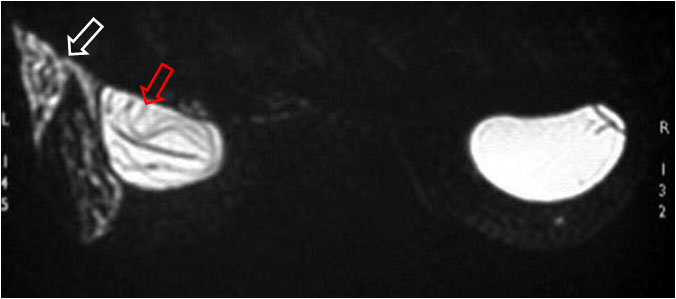

SIGNO DEL LINGUINE

Signo de rotura intracapsular de implante mamario de silicona en la Resonancia magnética. El implante roto presenta múltiples imágenes curvilíneas de baja señal en el interior de la hiperintensidad de la silicona. Es el signo más específico de rotura intracapsular. En la imagen puede verse el signo (flecha roja) y salida de silicona fuera del implante (flecha blanca)

El nombre «linguine» o «linguini» (el plural) hace referencia a un tipo de pasta larga y fina como spaguetti pero aplanada, más estrecha que los fetucini.

Referencia: Safvi A. Linguine sign. Radiology. 2000;216 (3): 838-9. http://pubs.rsna.org/doi/full/10.1148/radiology.216.3.r00se16838.